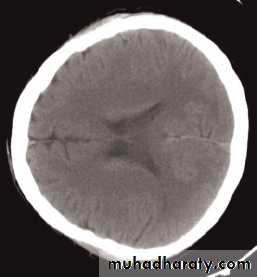

The cardinal signs of an abnormality on a CT scan are:

• Abnormal tissue density• Mass effect

• Enlargement of the ventricles.

Enlargement of ventricles

There are two basic mechanisms which cause the cerebral ventricles to enlarge:• Obstruction to the CSF pathway, either within the ventricular system (non-communicating hydrocephalus) or over the surface of the brain (communicating hydrocephalus)

• Secondary to atrophy of brain tissue